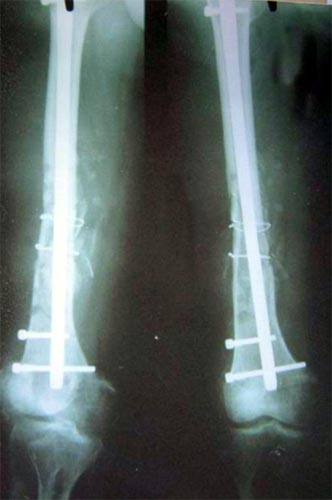

病例四、患者男性,13岁,股骨干中远1/3骨母细胞瘤,切除瘤体后形成大段骨缺损。我们用髓内钉和钢板内固定,大段异体骨植骨,骨生长因子和骨髓细胞的植入,骨缺损在12个月顺利愈合。